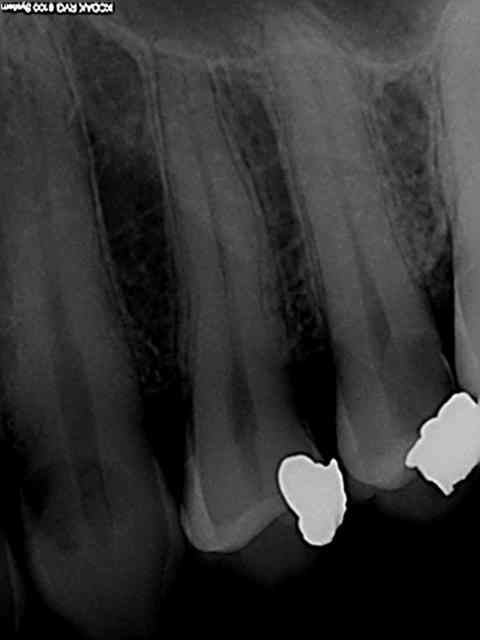

il y a quelques années, une dame se pointe avec son époux, avec un abcès paro sur une incisive mandibulaire. radio, anesthésie, débridement, irrigation, ordonnance, puis 20 mn de discussion au bureau car elle a une canine vestibulo-versée, elle ne sait pas quoi faire, extraction, ortho...

je lui facture un détartrage et une retro-alveolaire.